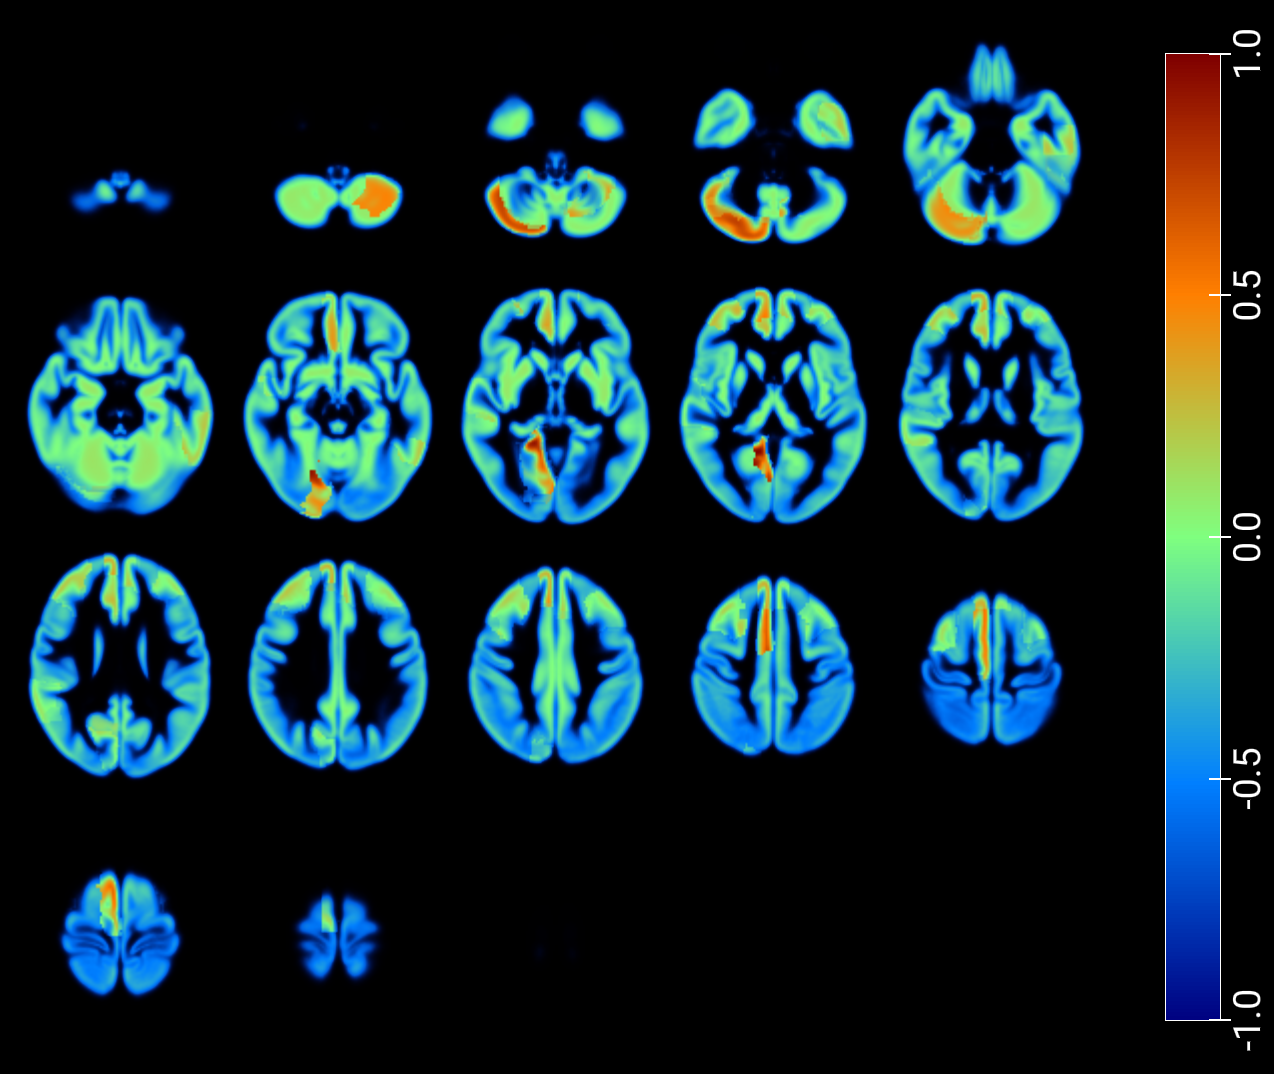

As a critical baseline, we report classification results based on latent features in [2] and provide visualizations of the maximum Pearson correlation values between latent-space activations -projected onto low-dimensional spaces- and region-wise average intensities, stratified by class, and fused with GM MRI (figures 7 and 8). These results explore the correspondence between network activations and anatomical signal distributions and whether it differs across clinical conditions (e.g., AD vs. NOR). This offers a transparent alternative to assess model interpretability and underscores the need for more rigorous and nuanced validation practices in the field.

An inspection of the groups and regions with the highest correlations reveals overlapping areas across clinically relevant comparisons in image reconstruction, as summarized for the t-SNE–based projections in Table 2. These regions correspond closely to those identified through the SHAP analysis presented in the following section (Table 3).

| NOR, AD | NOR, MCI | Cingulum_Mid_R, Frontal_Mid_L, Insula_R |

| NOR, MCI, MCIc, AD | Cerebelum_Crus2_R, Frontal_Mid_L, Insula_R | |

| NOR, MCIc | Frontal_Mid_L, Frontal_Mid_R, Frontal_Sup_L | |

| NOR, MCI | NOR, MCI, MCIc, AD | Frontal_Inf_Oper_L, Frontal_Mid_L, |

| Insula_R, Temporal_Mid_L | ||

| NOR, MCIc | Frontal_Mid_L, Temporal_Mid_L | |

| NOR, MCI, MCIc, AD | NOR, MCIc | Frontal_Mid_L, Heschl_L, Temporal_Mid_L |